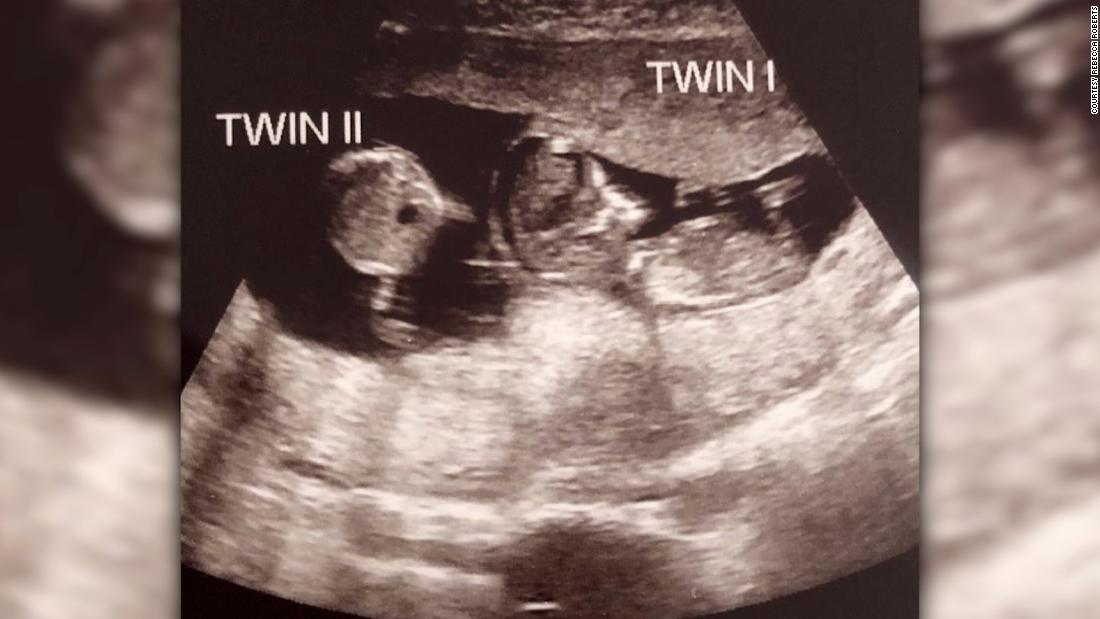

Nhưng sau đó, h́nh ảnh siêu âm được thực hiện ở tuần thứ 12 cho thấy Noah bất ngờ có một cô em gái nằm chung tử cung mẹ.

Ảnh chụp siêu âm bé Noah có em 3 tuần sau khi được thụ thai. Ảnh: CNN